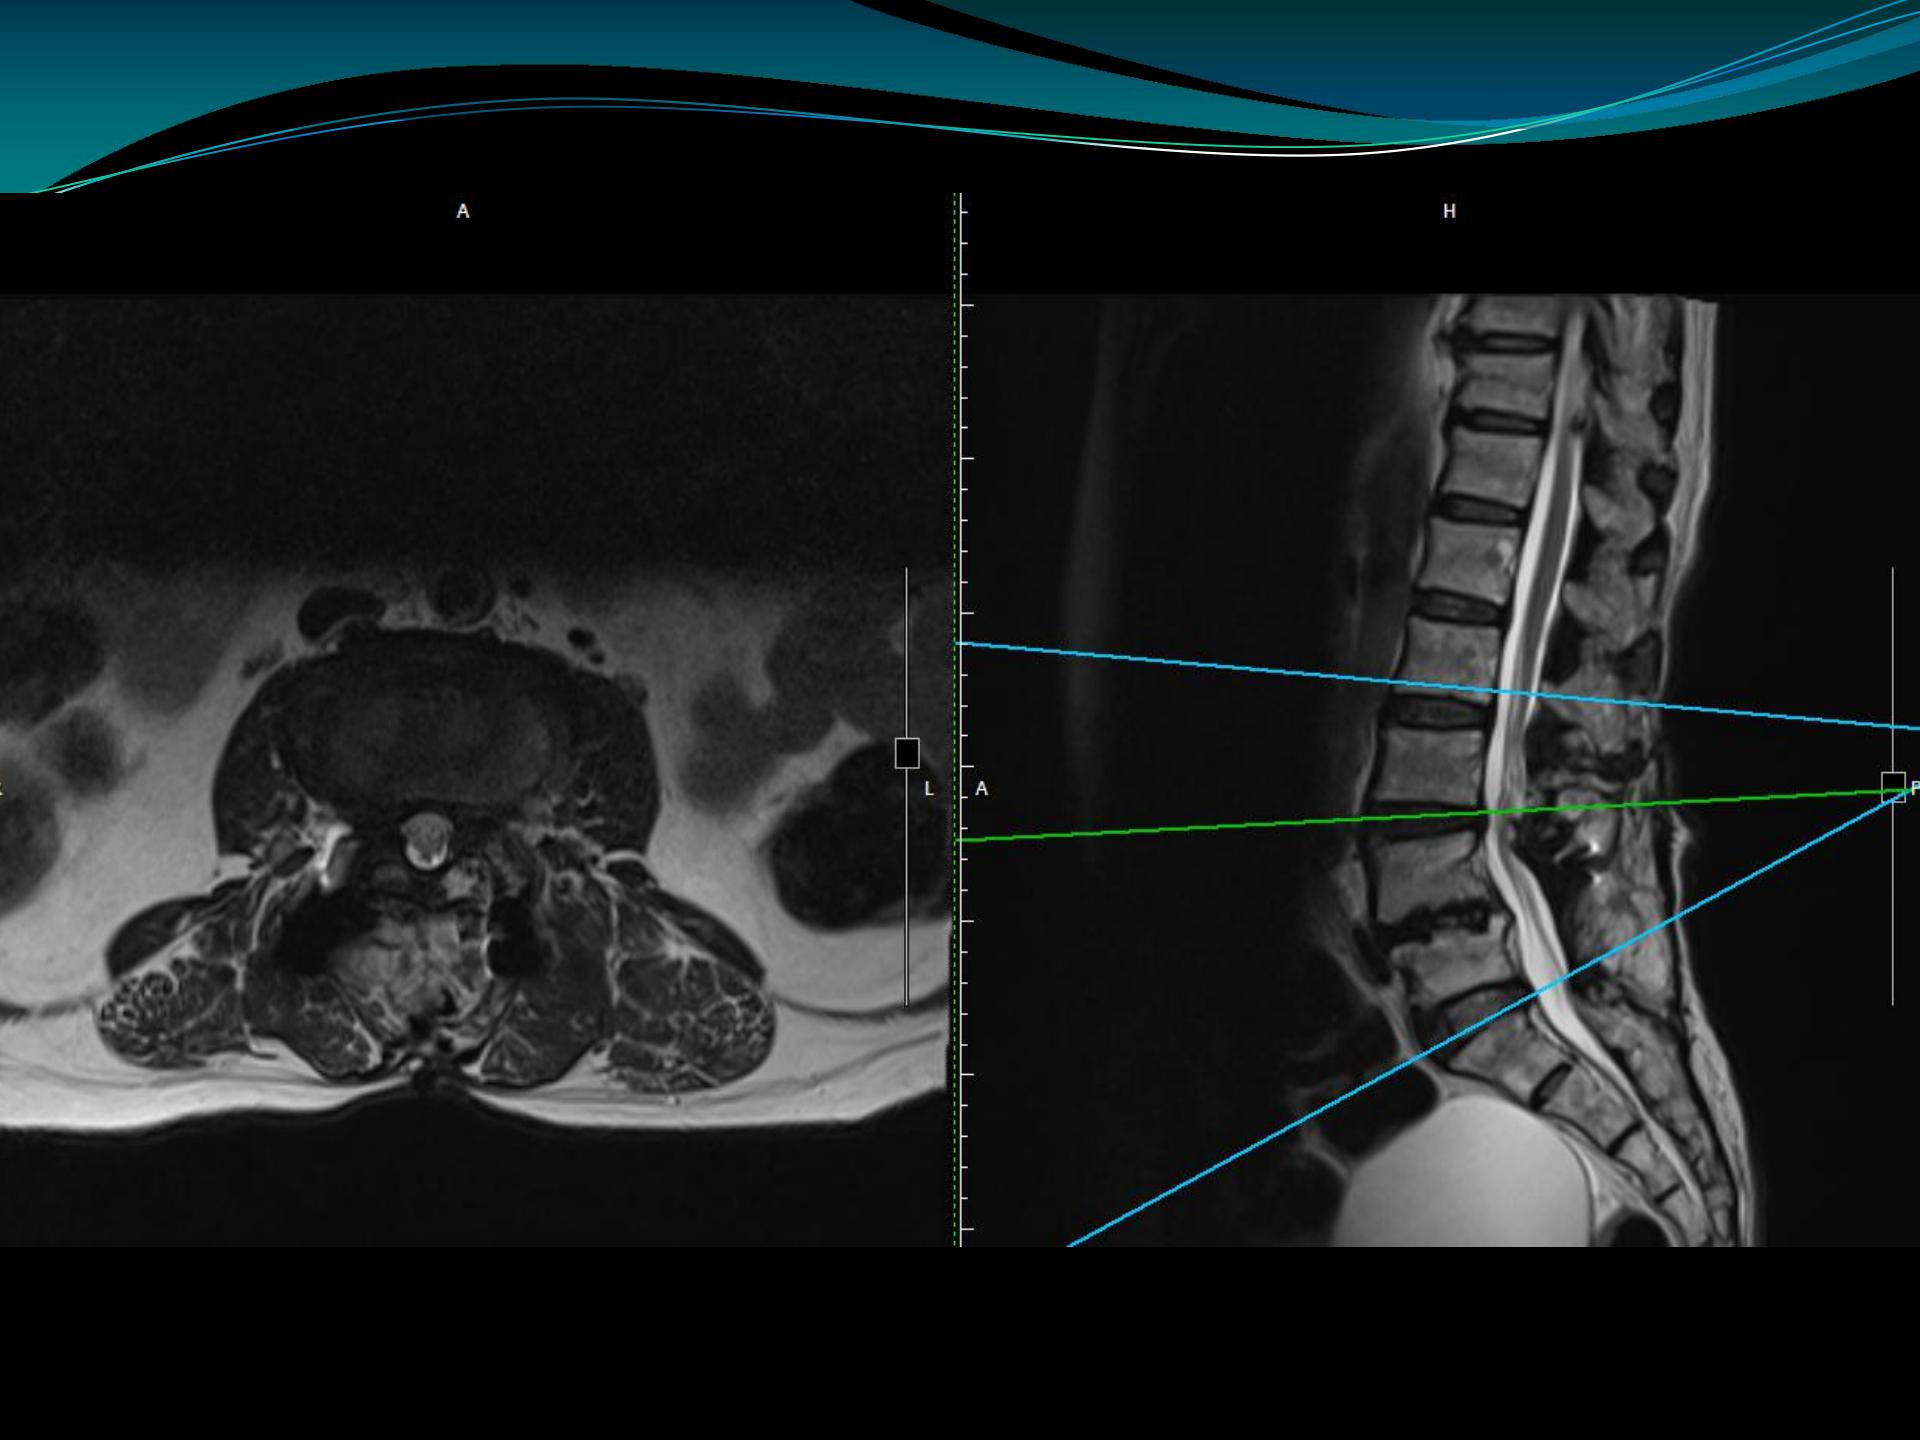

腰5骶1椎间孔狭窄

l4-5双侧椎间孔狭窄 l5-s1双侧侧隐窝狭窄